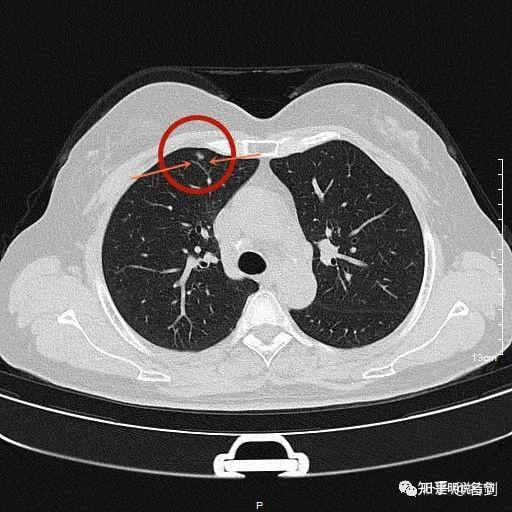

右肺上叶前段的部分实性结节边缘有毛刺,左肺上叶是纯磨玻璃结节

见右上叶前段磨玻璃结节先来看平扫的图像:病人某a,于今年4月份在本院